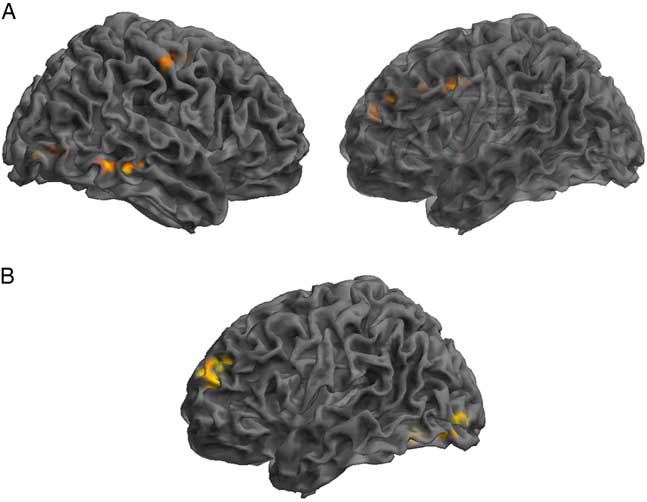

GICA Results: SRC Group Post-concussion Over Time

Assessment of the SRC group at time 1 (acute phase of SRC) compared to time 2 (when SRC symptoms should be resolved), revealed greater functional connectivity in the DMN components at time 1 compared to time 2 within the right IFG, MTG, precentral gyrus, and angular gyrus (AG), and left lingual gyrus, MFG, and middle cingulate gyrus (MCG). Decreased connectivity at time 1 compared to time 2 was found within the left anterior prefrontal cortex and MOG (Table 3; Figure 2).

Fig. 2 Significant changes in functional connectivity from time 1 to time 2 in the SRC group. (A) Greater connectivity and (B) reduced connectivity in the SRC group from time 1 to time 2. (A) Shown: right MTG, right precentral, left lingual gyrus, left MFG, left middle cingulate; Not shown: right angular gyrus. (B) Shown: left anterior PFC and MOG.

Table 3 Changes across time within the DMN component derived using GICA, assessing SRC group at time 1 compared to time 2

Time 1>Time 2 indicating brain regions with greater functional connectivity at time 1 compared to time 2 and Time 1<Time 2 indicating reduced functional connectivity at time 1 compared to time 2.

L=left hemisphere; R=right hemisphere; BA=Brodmann area; MOG=middle occipital gyrus; IFG=inferior frontal gyrus; MFG=middle frontal gyrus; MTG=middle temporal gyrus; PFC=prefrontal cortex.